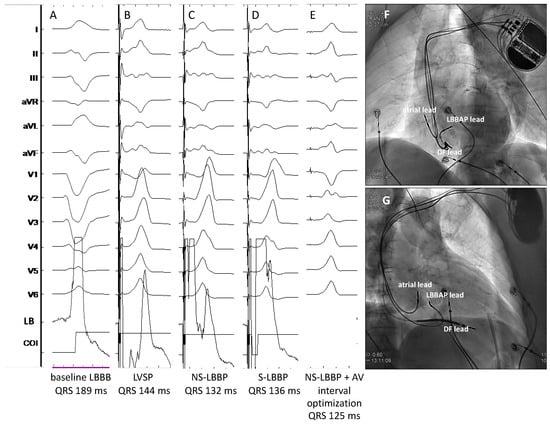

- Jastrzębski, M.; Moskal, P.; Huybrechts, W.; Curila, K.; Sreekumar, P.; Rademakers, L.M.; Ponnusamy, S.S.; Herweg, B.; Sharma, P.S.; Bednarek, A.; et al. Left bundle branch-optimized cardiac resynchronization therapy (LOT-CRT): Results from an international LBBAP collaborative study group. Heart Rhythm. 2022, 19, 13–21. [Google Scholar] [CrossRef] [PubMed]

- Feng, X.F.; Yang, L.C.; Zhao, Y.; Yu, Y.C.; Liu, B.; Li, Y.G. Effects of adaptive left bundle branch-optimized cardiac resynchronization therapy: A single centre experience. BMC Cardiovasc. Disord. 2022, 22, 360, Erratum in BMC Cardiovasc. Disord. 2022, 22, 558. [Google Scholar] [CrossRef]